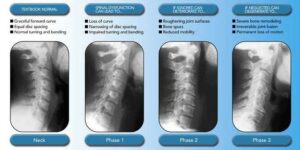

Phases of Spinal Degeneration

By the time I was 18 and had my very first chiropractic exam, I was already in Phase I of degenerative change. Degeneration of the spine is progressive in nature and will continue unless an intervention is applied. I’m so grateful that the intervention was chiropractic. Look at the picture below to see how these phases progress if not taken care of:

Wolff’s Law states that bone will adapt to the load or stress placed upon it. This means that increased loading of bone tissue will promote increased density. This is why many individuals with osteopenia or osteoporosis utilize resistance training to stimulate bone growth. However, when the stress or load on the bone is abnormally loaded, Wolff’s Law can contribute to the progression of spinal degeneration.

In the spine, a similar process plays out with spinal degeneration. As abnormal pressure builds up on the segments of the spine, the increased demand requires more support. The wear and tear associated with increased stress around the joints of the spine will stimulate bone cells to produce hardened tissue to help support the abnormal load. This makes the spine more rigid, and spinal degeneration begins to advance.